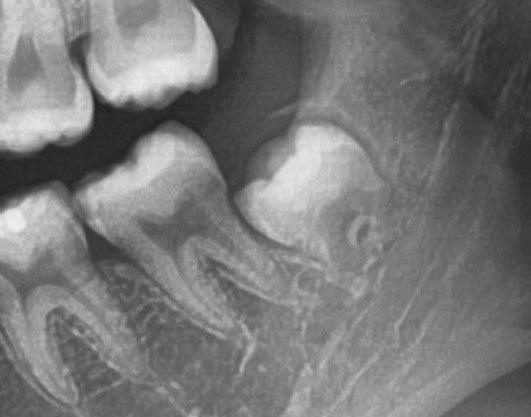

Dalla radiografia (Fig. 166) sembrava che il dente avesse due radici separate, quindi è stato eseguito un taglio orizzontale utilizzando il manipolo dritto per sezionare il dente a metà. Tuttavia, la corona si è frat-

turata poiché in realtà le radici erano unite e il dente non è stato sezionato completamente.